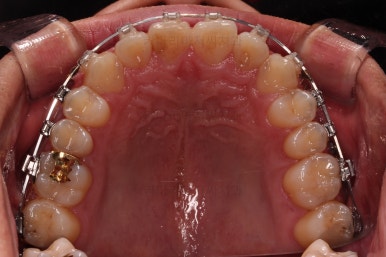

초진 시 입안의 모습입니다.

비교적 고른 편이긴 하나 아랫니가 전반적으로 밀려 나오면서 앞니끼리 부딪혀 있는 양상이고요.

어금니 맞물림도 긴밀하게 톱니바퀴처럼 위아래가 맞물려 있는게 아니라 엉성한 모습이죠.

앵글씨 3급 부정교합이라고 하는데요.